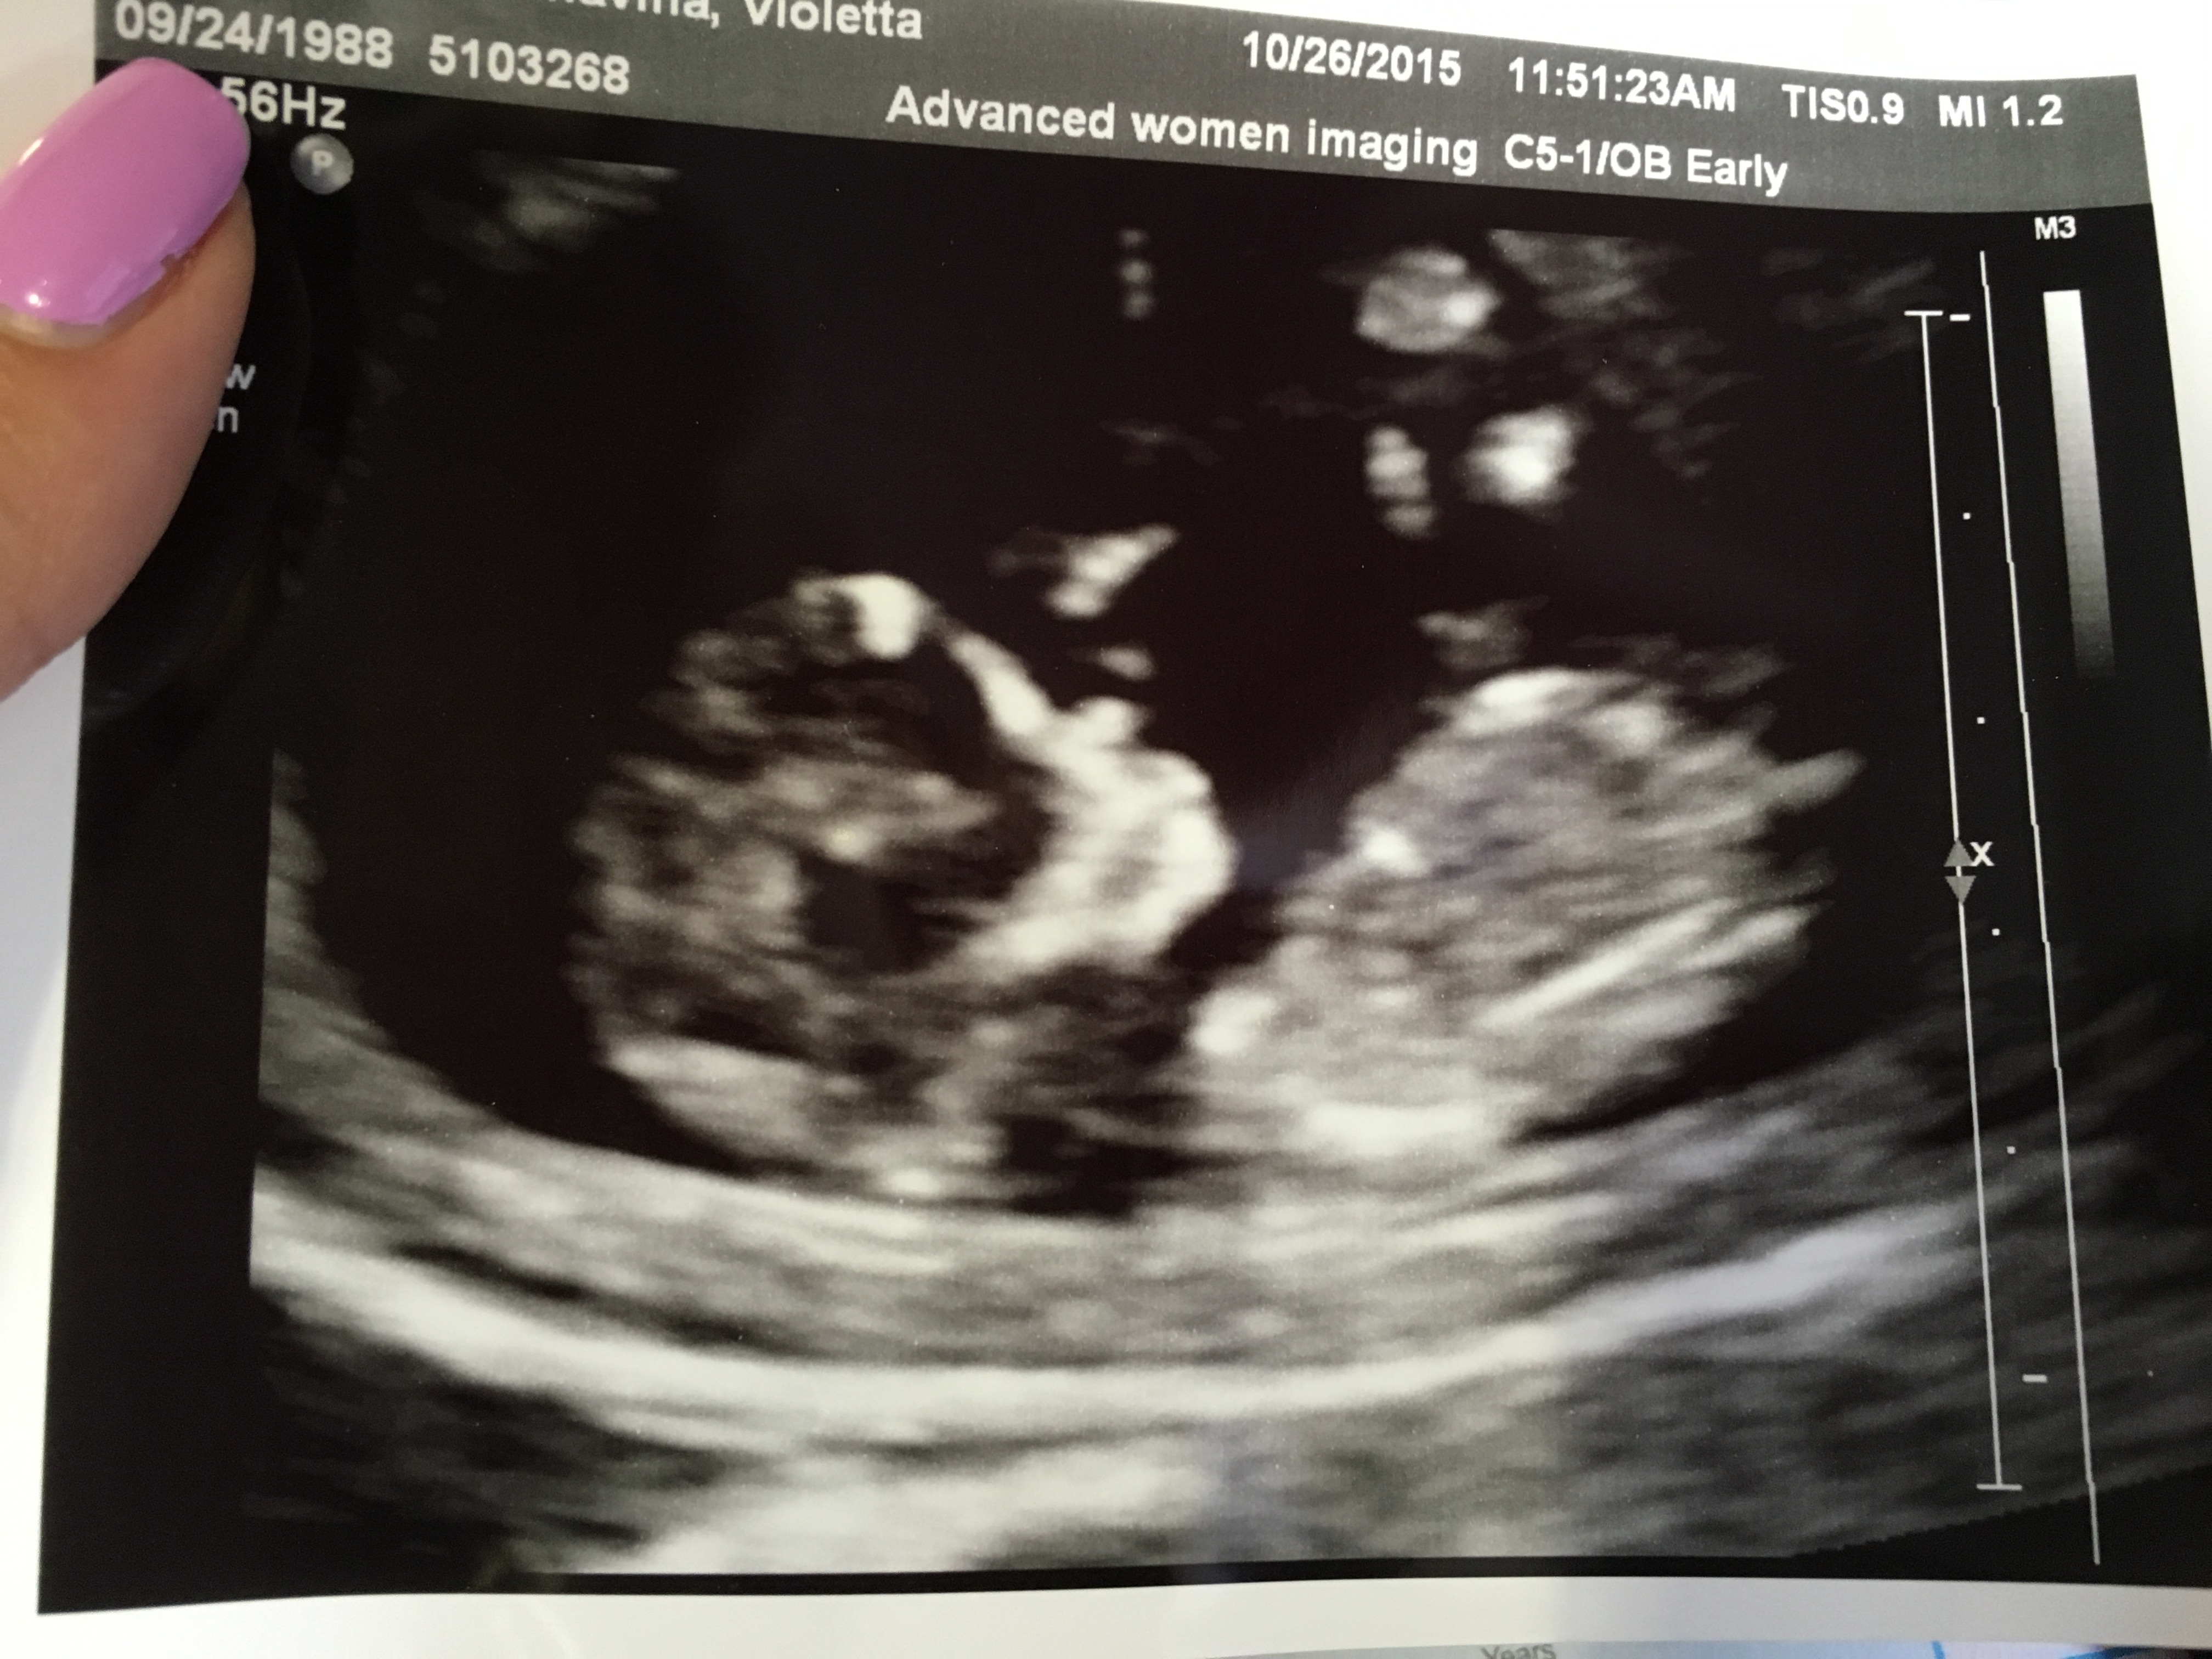

@kbrands7 I missed why you had to have the ultrasound but so relieved for you things are good. But now, can we talk about those baby fingers?!?! Aghhh can't wait for my next scan, so precious!!

I love the fingers too! It was so amazing to see little one bopping around and putting fingers in his/her mouth. :x I hope you get to see some cuteness (and of course a healthy baby) during your next scan!